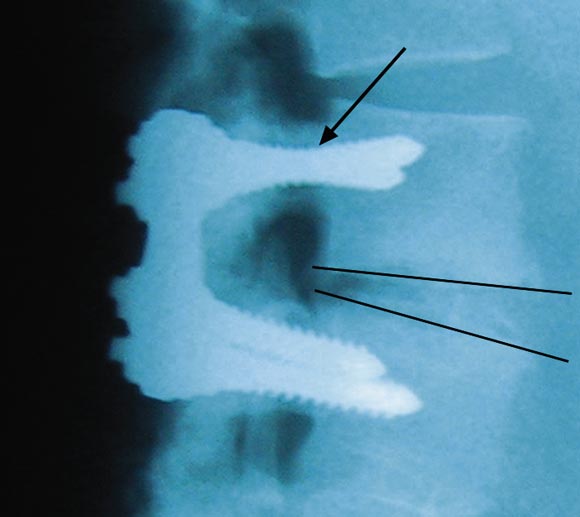

Our two patients were in their late 40s when severe vitamin D deficiency became apparent. In the first patient, recurrent pain a short time after surgery was of such severity that internal fixation plates had to be removed. The screws were loose, and, in the absence of infection, the profound vitamin D deficiency can be assumed to have resulted in failure of mineralisation of osteoid and hence failure of the surgical procedure, with resulting increased morbidity.